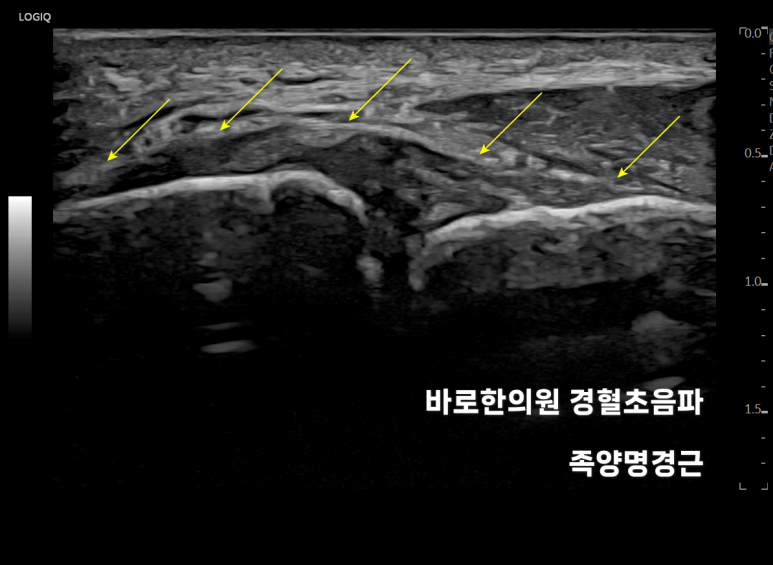

영상에서

전하경비인대는 이렇게 보입니다.

인대 내부 섬유 패턴이

하얗게 잘 보이면서 인대 표면이

경골과 비골을 연결하는 선을넘어가지 않습니다. 그런데 위 환자분은

없어지면서 까맣게 보이고요. 인대가 늘어나

많이 부어있는 상태였습니다.

이렇게 로

문제가 있는 혈 자리를 찾아정확한 깊이로 시술해야 합니다.*